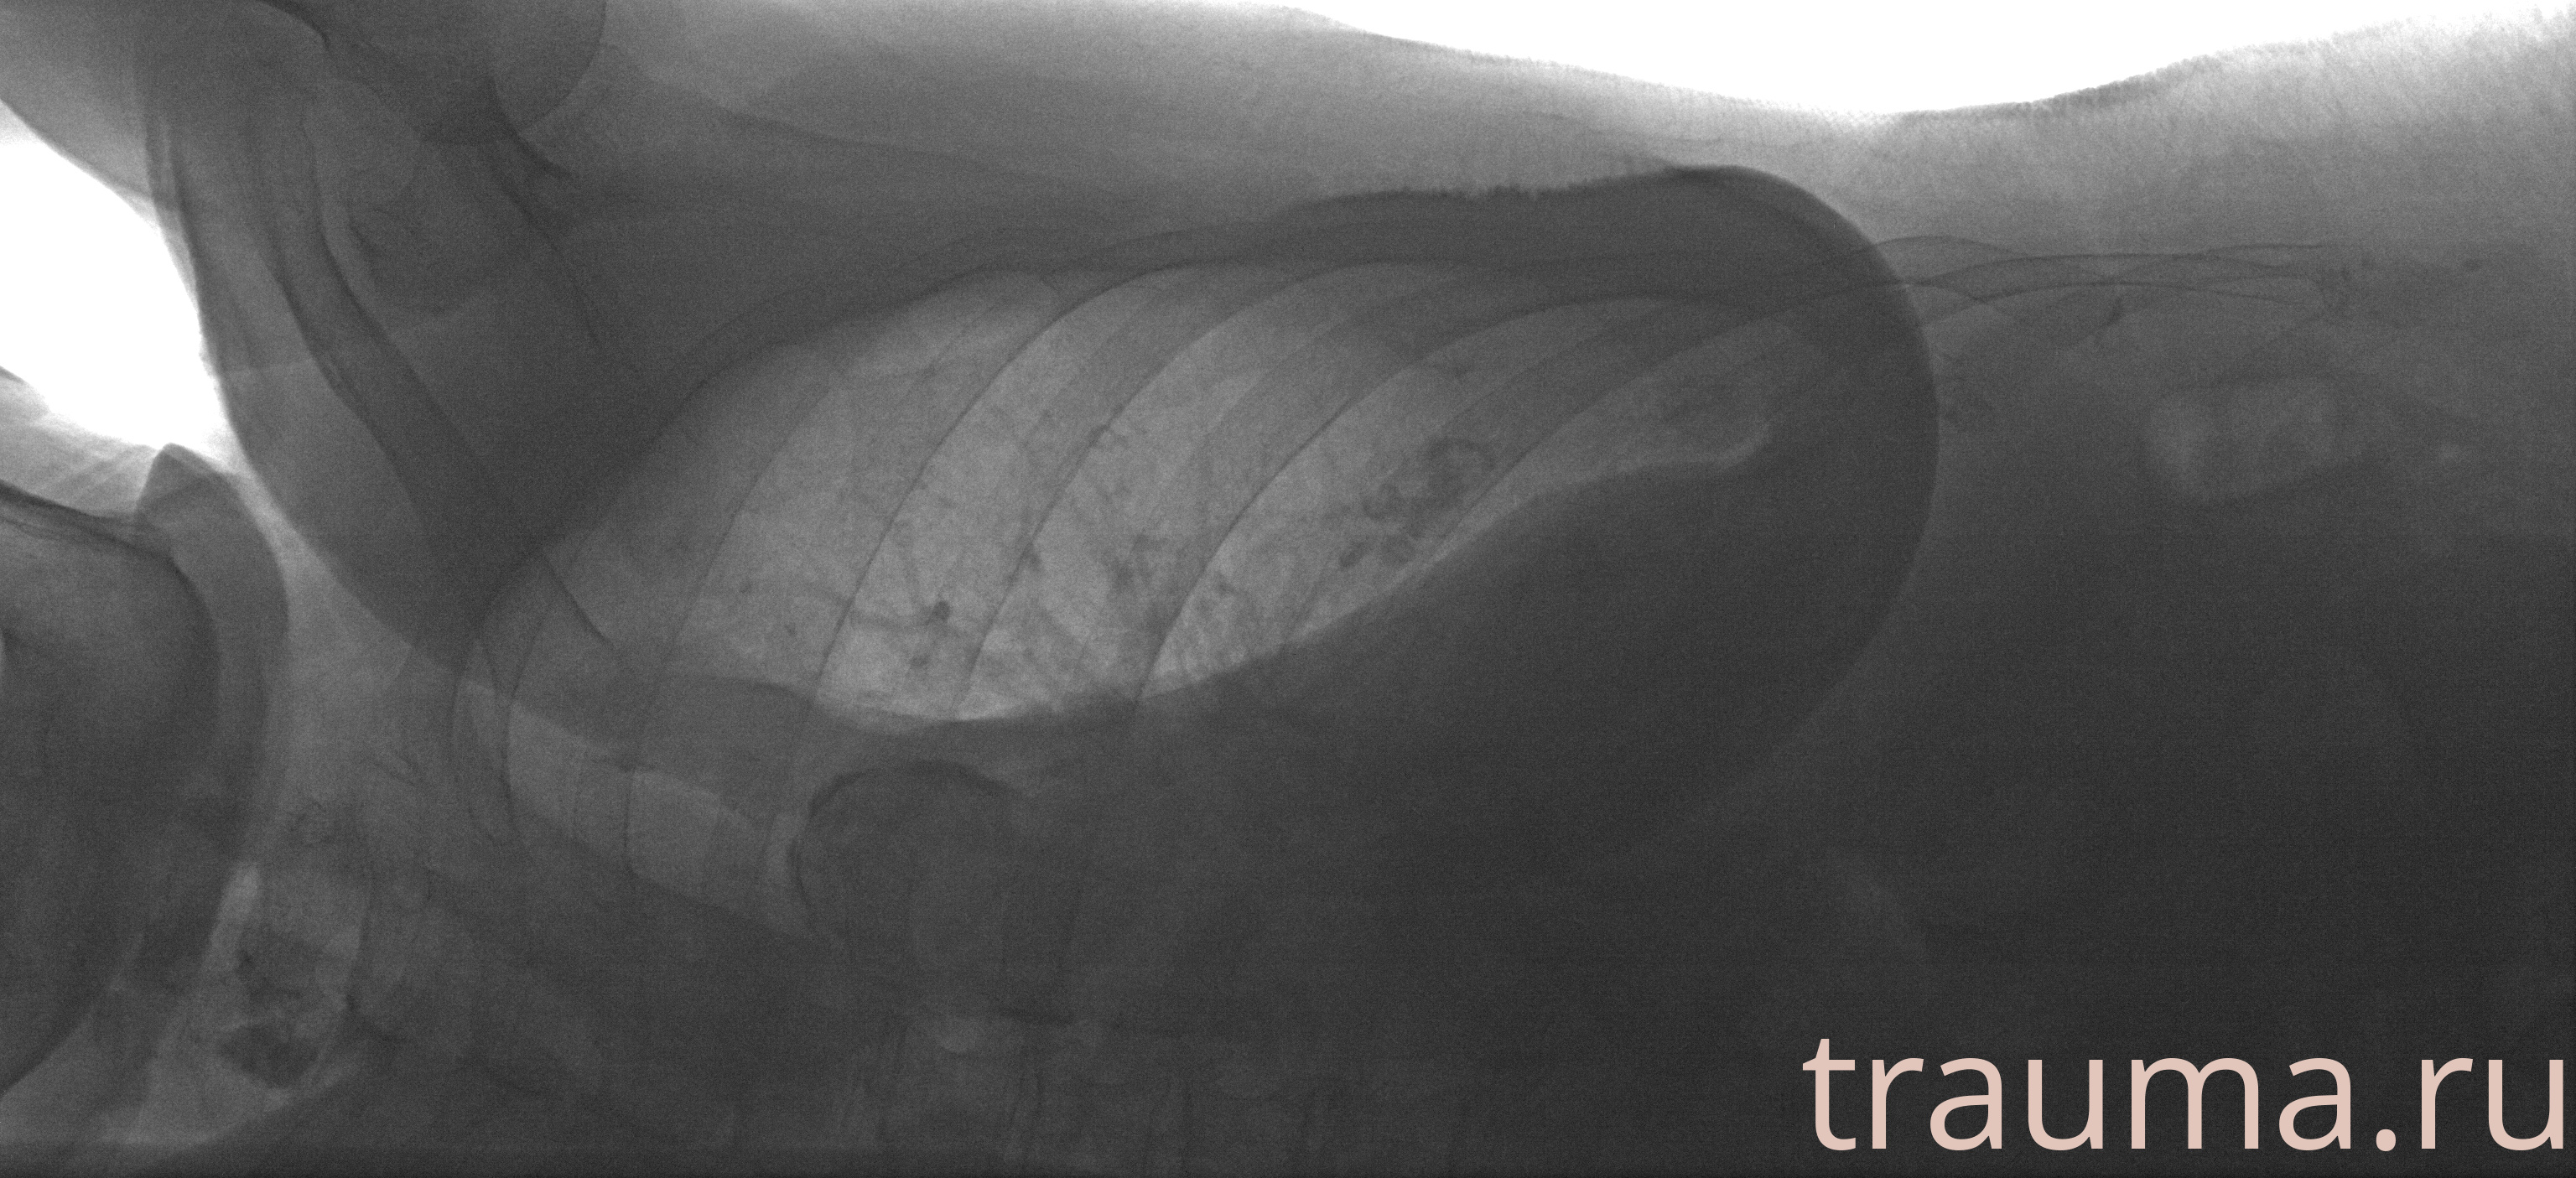

Рентгенограммы

Рентген на дому: по вашему адресу приезжает врач-рентгенолог, травматолог-ортопед с мобильным рентгеновским аппаратом, проводит диагностику травмы или заболевания, делает необходимые рентгенограммы, дает рекомендации по дальнейшему лечению. Получить качественные снимки в домашних условиях возможно благодаря уникальной методике, разработанной МосРентген Центром для института  Склифосовского

при переломе шейки бедра и пневмонии от компании МосРентген Центр - партнера Института имени Склифосовского